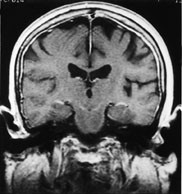

Durale metastaser fremtrer som kurvilineære streker med patologisk signaløkning etter kontrast. Disse strekene skal følge skalletakets innside og ikke gå inn i sulci på hjernens overflate (fig 9). Signaløkningen kan være segmental eller følge skalletaket i hele omkretsen. Segmental signaløkning skal være til stede på flere nærliggende snitt. Atskillelsen mot den lette fysiologiske kontrastoppladning i dura kan være vanskelig. Durale metastaser kan også ha et fokalt preg.

Leptomeningeal tumor fremtrer som tynne streker med kontrastoppladning som følger gyri dypt inn i sulci (fig 10), eventuelt som små knuter på hjernens overflate eller et tynt lag med patologisk kontrast utenpå hjernestamme eller hjernenerver. Ettersom arachnoidea ligger tett inntil det indre laget av dura, kan dural-araknoidal tumor ikke med sikkerhet skilles fra pial-subaraknoidal tumor. Påvisning av en dural-araknoidal patologisk signaløkning utelukker dermed ikke samtidig forekomst av tumor i pia eller subaraknoidalrom.

Hydrocephalus kan være uttrykk for at resorpsjonen av cerebrospinalvæske på overflaten er redusert som følge av diffus tumorutsæd i pia (fig 10).